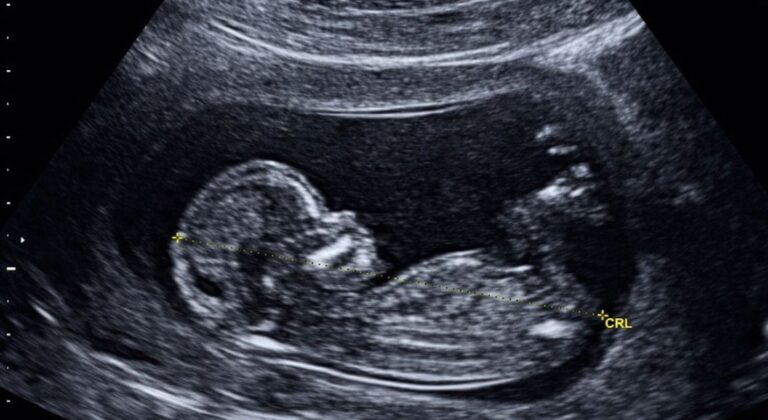

La medida priorizó la decisión de la mujer gestante y el interés superior del niño